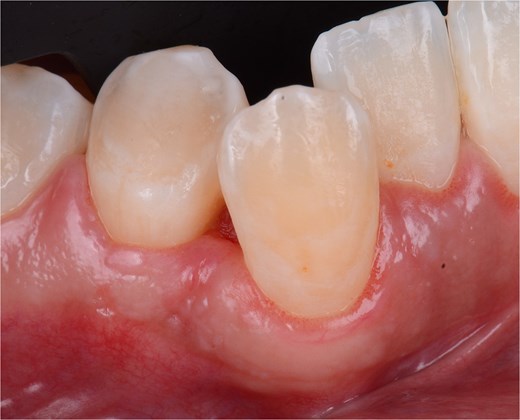

A 29-year-old female patient with no pathological history and healthy periodontium visited the dental clinic with the following complaint: ‘When I was pregnant, a small lump appeared on my gum that bled and would not go away.’ Intraoral examination revealed a mucogingival tissue growth on the attached gum, which was firm, oval, fibrous, smooth, and without signs of active ulceration, measuring ~ 1 × 0.5 cm. The lesion originated at the base of the papilla and part of the adjacent masticatory mucosa, presenting a pedunculated base that extended to the interproximal region of teeth 43 and 44, with erythematous coloration and whitish areas (Fig. 5). The patient reported pain on palpation, with no history of trauma or surgery in the area. A digital periapical radiograph was taken to rule out periodontal or infectious pathology at the bone level.

Front view of the clinical image of the intraoral lesion: Growth of mucogingival tissue in the attached gingiva, with a firm, oval, fibrous, smooth appearance and without signs of active ulceration.